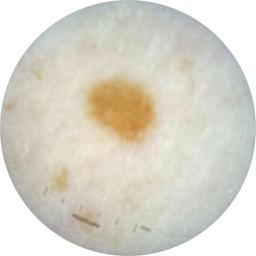

ISIC_9785574

Information

2003 x 2003

Attribute to

MEL-SELF Trial, https://www.sydney.edu.au/medicine-health/our-research/research-centres/melself-project.html

License

Clinical

Field Value

acquisition_day 148

age_approx 45

anatom_site_1 Head and neck

anatom_site_general head/neck

concomitant_biopsy False

diagnosis_1 Benign

diagnosis_confirm_type single image expert consensus

family_hx_mm True

image_manipulation instrument only

image_type dermoscopic

lesion_id IL_0236417

patient_id IP_8456088

personal_hx_mm True

sex female